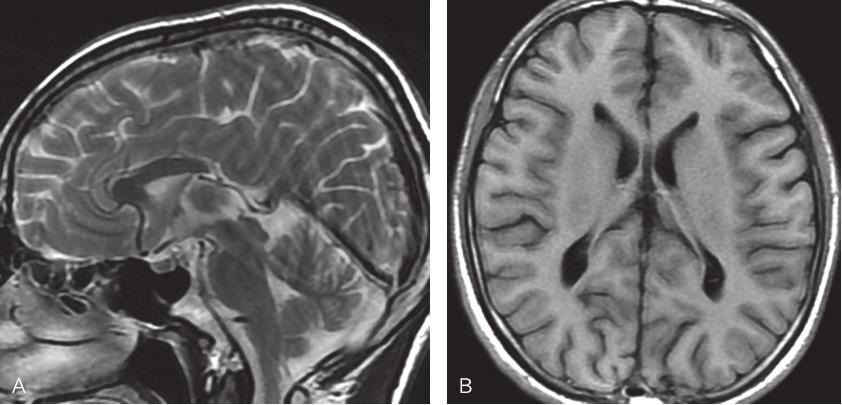

图2-3-2 胼胝体完全缺失MRI表现

A.矢状位T 2 WI示胼胝体完全性缺失,第三脑室扩张并向上移位,扣带回呈放射状分布,胼周动脉垂直向上走行;B.冠状位T 1 WI示脑纵裂池向下延伸至第三脑室顶,侧脑室呈“公牛角”样改变;C、D.横断位T 2 WI示双侧侧脑室平行分离,侧脑室后角及三角区扩张,侧脑室前角变窄,第三脑室扩张并上移位至分离的两侧侧脑室之间